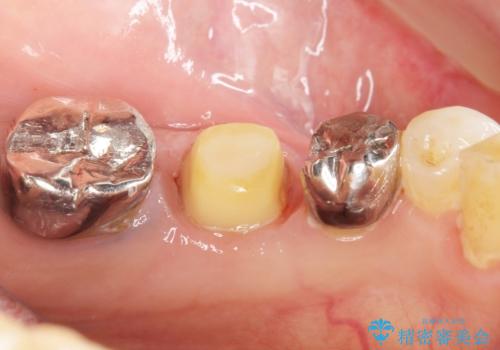

保存不可能な奥歯(左下6)を抜歯し、機能していない親知らず(左下8)の移植を行いました。

移植後、生着を待って根管治療及び補綴修復を行いました。

機能していない親知らずを用いて咬合を回復することができ、喜んで頂けました。

被せ物の種類:メタルボンドクラウン エコノミー